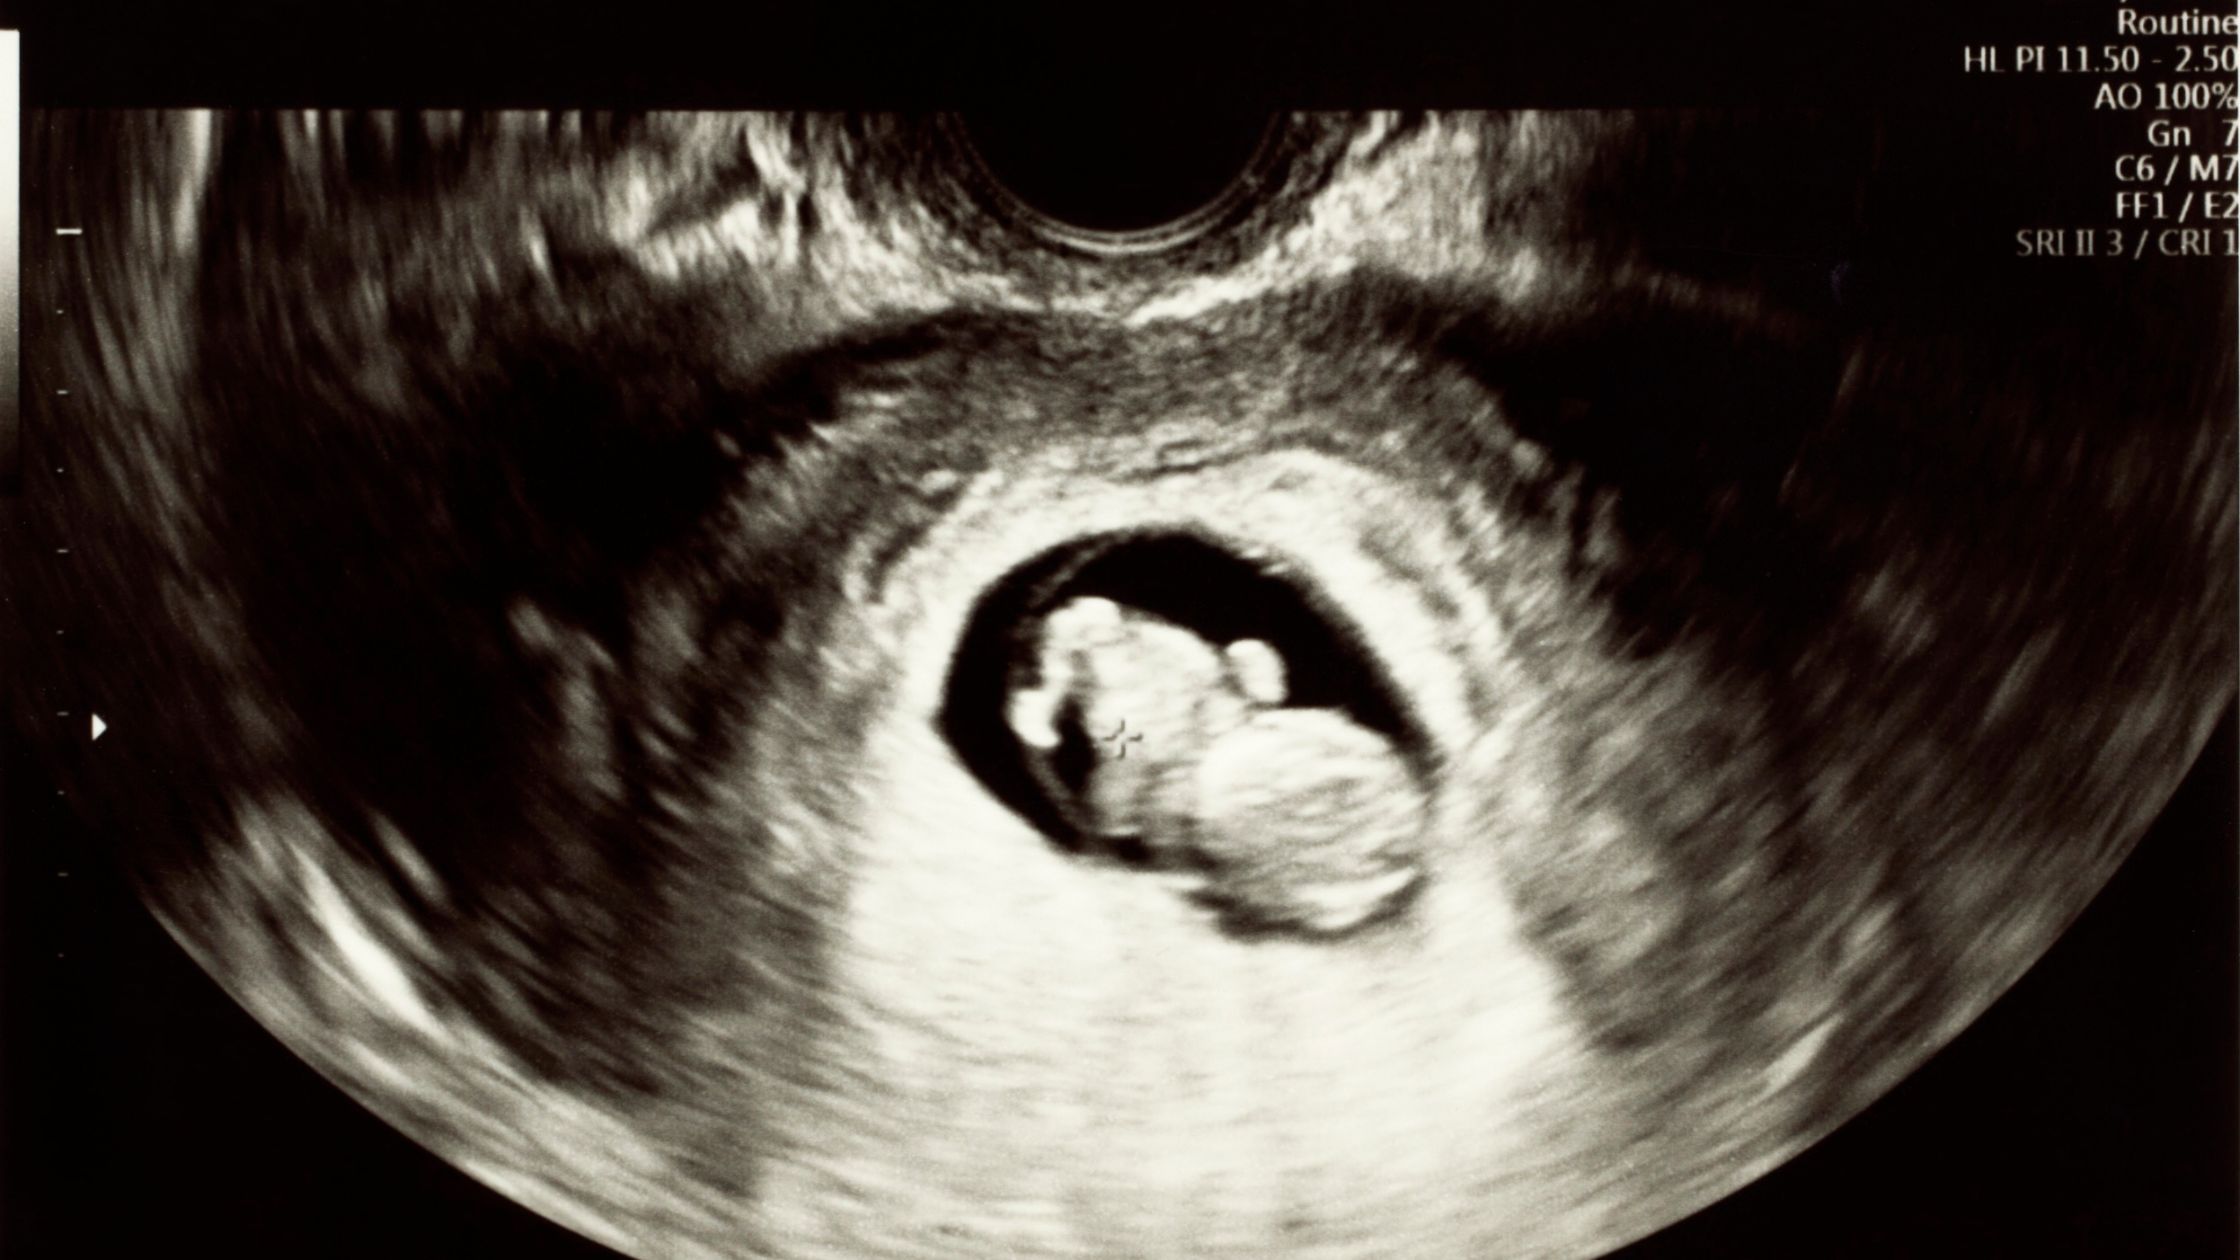

Q1: Is the fetus at one month visible on ultrasound?

At one month, the embryo is extremely small—an ultrasound may not yet show a fetal image clearly.